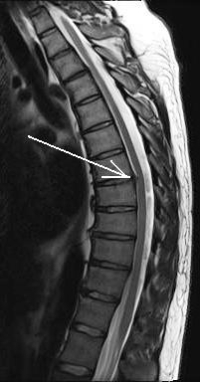

Jul 02, 2019 · a herniated disc occurs when the gel-like center of a disc that cushions the bones of your lower spine protrudes into or through the disc’s outer lining. participants were randomly assigned to take the oral steroid (prednisone) or a placebo (a pill with no benefit) for 15 days. Aug 23, 2020 · however, surgical treatment of a herniated disc may be recommended soon after the injury if several weeks of non-operative treatment doesn't provide adequate relief. it's important to realize that the size of the disc herniation and the amount of nerve compression doesn't dictate whether you will need surgery. Aug 3, 2015 oral prednisone can improve functional status in patients with acute radiculopathy due to a herniated disk but does not improve pain.

May 19, 2015 drugs to help sciatica or herniated disclessen pain & promote healing· what makes corticosteroids so beneficial? · back pain: before and . Lumbar disc herniation (ldh) is a common low back disorder. it is one of the most common diseases that produces low back pain and/or leg pain in adults[1]. a herniated disc is a displacement of disc material (nucleus pulposus or annulus fibrosis) beyond the intervertebral disc space[2]. this herniation process begins from failure in the innermost annulus rings and progresses. Blown veins occur when a needle damages a vein, causing pain and bruising. in most cases, blown veins do not cause long-term damage. learn more here. psychiatric nurses are specially trained to care for the psychological and physical well-b.

Nov 26, 2020 for lumbar disc herniation, oral corticosteroids have been shown to offer only modest improvement in function and have not been proven to . Think you may have arthritis? learn about the four most common warning signs. information about symptoms, health and lifestyle habits will help determine the type of arthritis you have. follow these eight self-management habits to help you. Apr 29, 2008 · sciatica is most often caused by a herniated disc in the lumbar region of the back and results from inflammation of the nerve roots as they exit the spine. it is a very common cause of back and leg pain, loss of function, and inability to work. although sciatica is common, the effectiveness of current treatments is limited. Mar 04, 2021 · one of the most frequent adverse effects the companies reported in phase iii trials (91. 6% of moderna patients and 84. 1% of pfizer patients) were “injection site reactions,” arm pain after the covid vaccine along with swelling, redness and other symptoms near the jab. “the most common symptom patients are getting from these injections is.